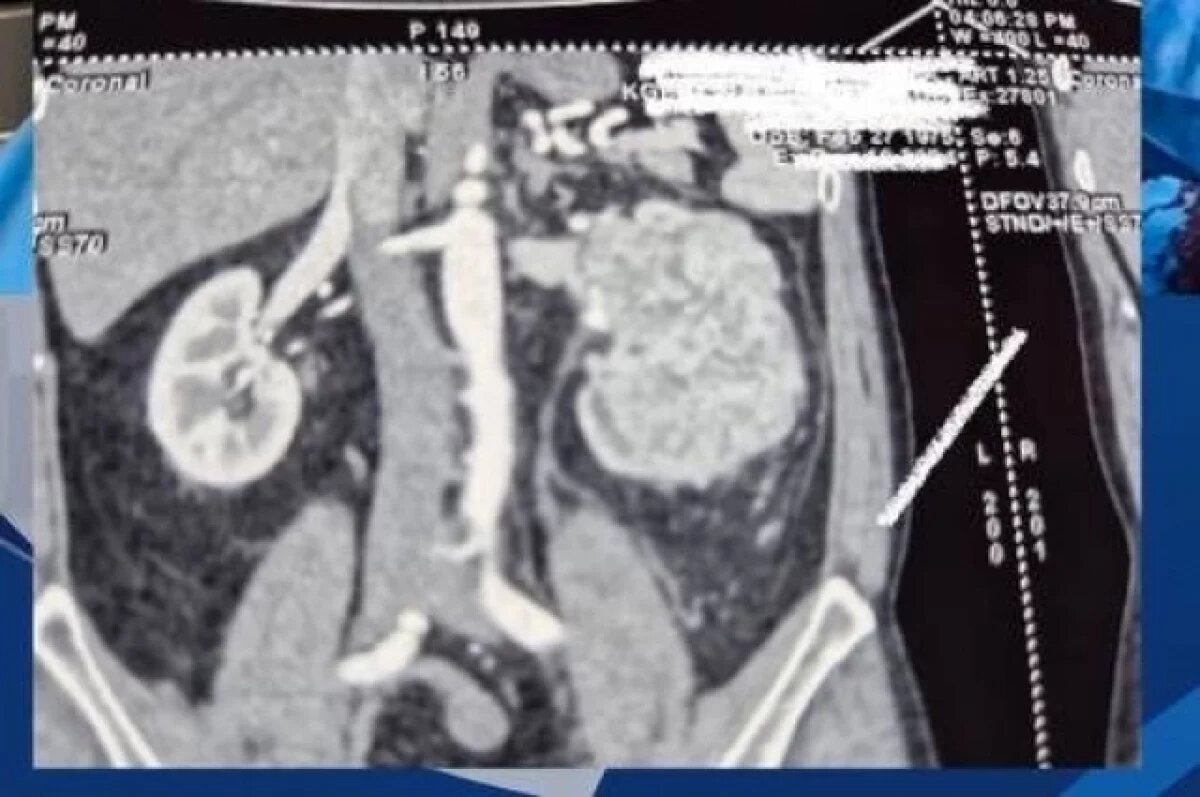

Врачи-онкоурологи во Владивостоке успешно провели сложнейшую операцию по удалению крупной опухоли почки у пациента в возрасте 50 лет.

Новообразование размером более 20 см проросло в толстую кишку. Также были подозрения на тромбоз. Кроме того, у пациента было сопутствующее заболевание, а именно гепатит С, что делало операцию опасной для жизни.

«Мы также сомневались в возможности проведения операции. Компьютерная томография показала, что опухоль проросла в толстую кишку и, возможно, тромб распространился за диафрагму и печень», - рассказала заведующая отделением онкоурологии КГАУЗ ВКБ №2 «1000-коечная больница» Галина Алексеева.